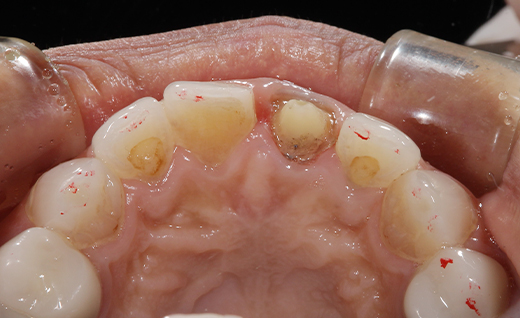

施術後

施術後です。施術前と比べるととても自然に見えるのが分かると思います。

オールセラミックは自然な見た目が特長であり、変色も少ないです。口元が自然で美しく見えることは、自信を持つ上で重要だと考えています。